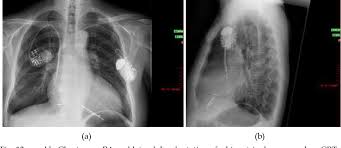

Sometimes, pacemaker and icd leads stop working properly due to damage or scar tissue accumulation. Pacemaker and icd troubleshooting, 2016. Like a pacemaker, an implantable cardioverter defibrillator, or icd, is a device placed under your skin. Implantable cardioverter defibrillators (icds) have a similar appearance to pacemakers. Implanting a pacemaker in your chest requires a surgical procedure. Temporary or permanent modification of the function (i.e., damage). Implantable cardiac conduction devices (also known as cardiac implantable electronic devices or cieds) are a very common medical device of the thorax cardiac pacemakers may be temporary or permanent, with the latter commonly known by the acronym ppm (permanent pacemaker). Pacemaker and icd manufacturers are arranged in alphabetical order with devices organized in numeric sequence.

Sometimes, pacemaker and icd leads stop working properly due to damage or scar tissue accumulation. An implantable cardioverter defibrillator (icd) looks similar to a pacemaker, though slightly larger. Which pacemaker/icd is that again. A pacemaker is a small device implanted in the chest. Pacemaker & icd are two different devices. Start studying pacemakers & icds. Movement and/or vibration of the pulse generator or leads. Die icd elektroden liegen regelrecht im rechten vorhof und im rechten ventrikel. Doctors also treat arrhythmias with implantable cardioverter defibrillators (icds). Icds are similar to pacemakers. Another type of pacemaker is called a biventricular pacemaker. Pacemaker and icd troubleshooting, 2016. Paces the heart muscles by providing an electrical.

Implanting a pacemaker in your chest requires a surgical procedure. Pacemaker and icd troubleshooting, 2016. How does a pacemaker work? It also contains a computer that tracks your national heart, lung, and blood institute: Another type of pacemaker is called a biventricular pacemaker. An implantable cardioverter defibrillator (icd) looks similar to a pacemaker, though slightly larger. Once the wires are in place, your doctor will make a small cut into the. Temporary or permanent modification of the function (i.e., damage). ©2021 daily search trends feedback. Pertinent factors relating to each manufacturer's devices are referenced according to: Devices that may interfere with icds and pacemakers. It works very much like a pacemaker. While pacemaker's job is to treat slow heart rate, icd's job is to treat very fast chaotic heart rhythm.